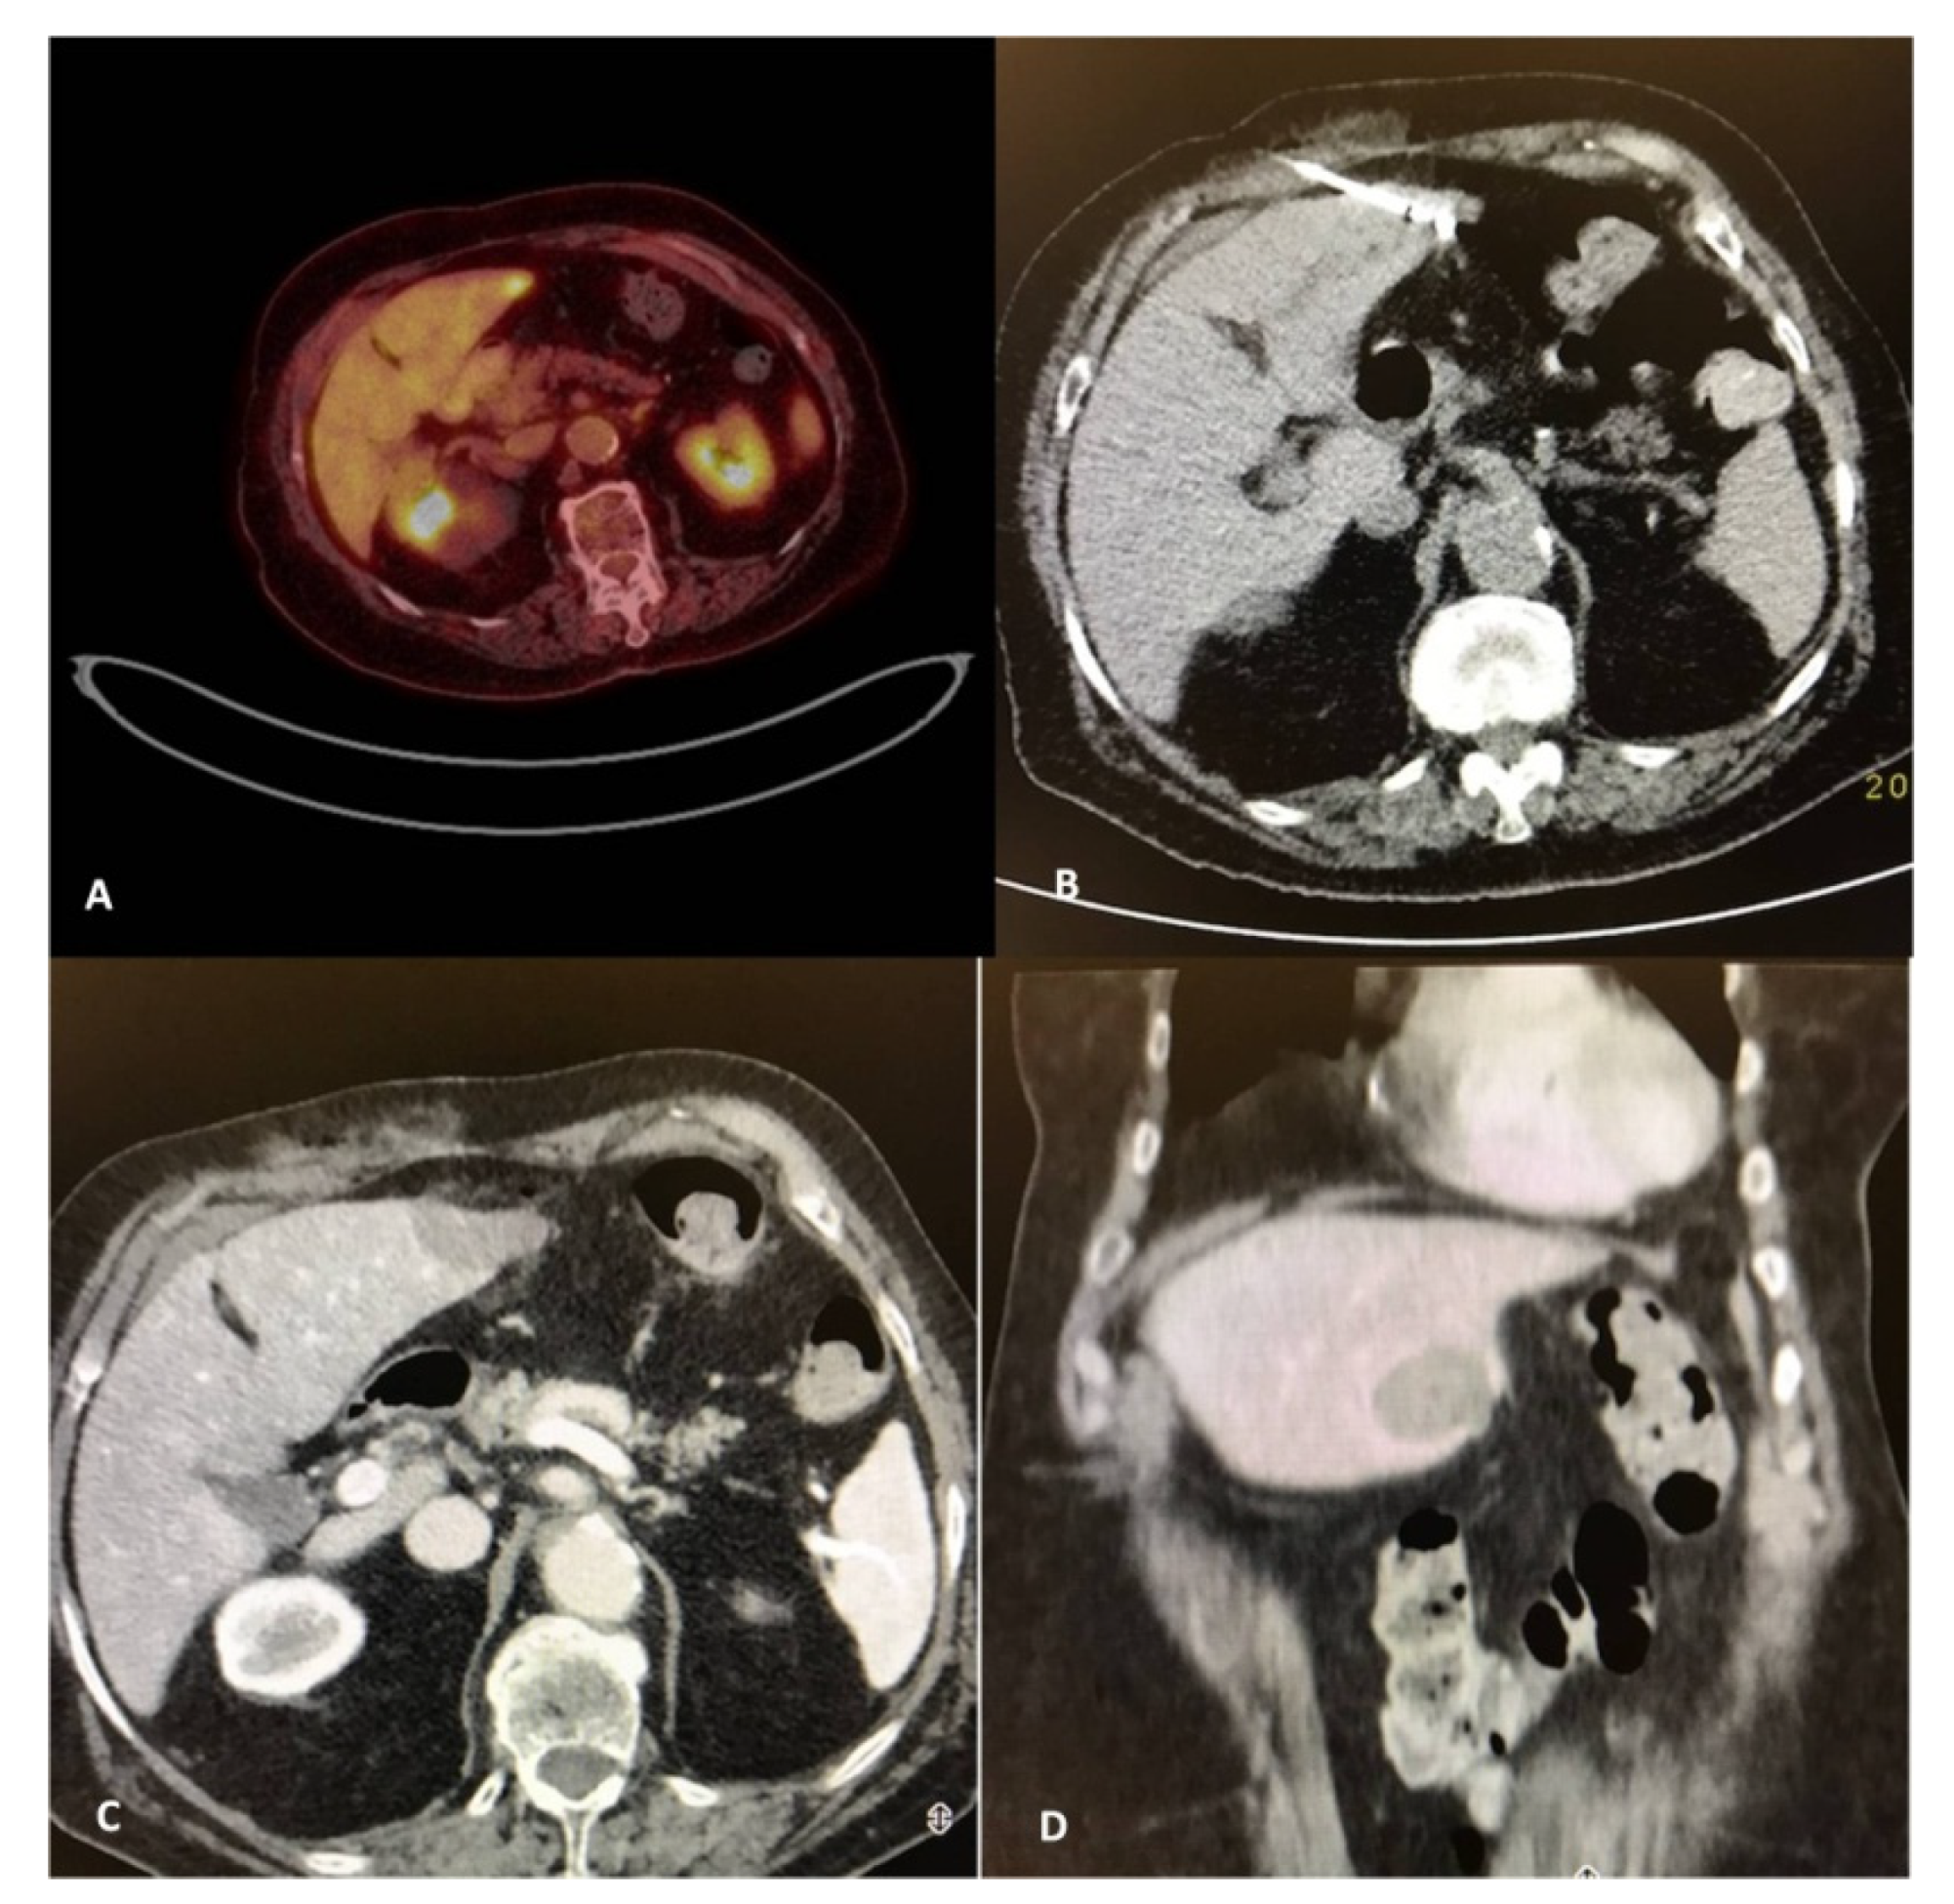

- Cornelis, F.; Sotirchos, V.; Violari, E.; Sofocleous, C.T.; Schoder, H.; Durack, J.C.; Siegelbaum, R.H.; Maybody, M.; Humm, J.; Solomon, S.B. 18F-FDG PET/CT is an immediate imaging biomarker of treatment success after liver metastasis ablation. J. Nucl. Med. 2016, 57, 1052–1057. [Google Scholar] [CrossRef]

- Ryan, E.R.; Sofocleous, C.T.; Schöder, H.; Carrasquillo, J.A.; Nehmeh, S.; Larson, S.M.; Thornton, R.; Siegelbaum, R.H.; Erinjeri, J.P.; Solomon, S.B. Split-dose technique for FDG PET/CT-guided percutaneous ablation: A method to facilitate lesion targeting and to provide immediate assessment of treatment effectiveness. Radiology 2013, 268, 288–295. [Google Scholar] [CrossRef]

- Cornelis, F.H.; Petre, E.N.; Vakiani, E.; Klimstra, D.; Durack, J.C.; Gonen, M.; Osborne, J.; Solomon, S.B.; Sofocleous, C.T. Immediate postablation 18F-FDG injection and corresponding SUV are surrogate biomarkers of local tumor progression after thermal ablation of colorectal carcinoma liver metastases. J. Nucl. Med. 2018, 59, 1360–1365. [Google Scholar] [CrossRef]

- Tsitskari, M.; Filippiadis, D.; Zavridis, P.; Mazioti, A.; Vrachliotis, T.; Alevizos, L.; Brountzos, E.; Kelekis, N. Efficacy and safety of percutaneous computed tomography-guided microwave ablation for colorectal cancer, oligometastatic liver-only disease: A single center’s experience. Ann. Gastroenterol. 2021, 34, 61–67. [Google Scholar] [CrossRef]